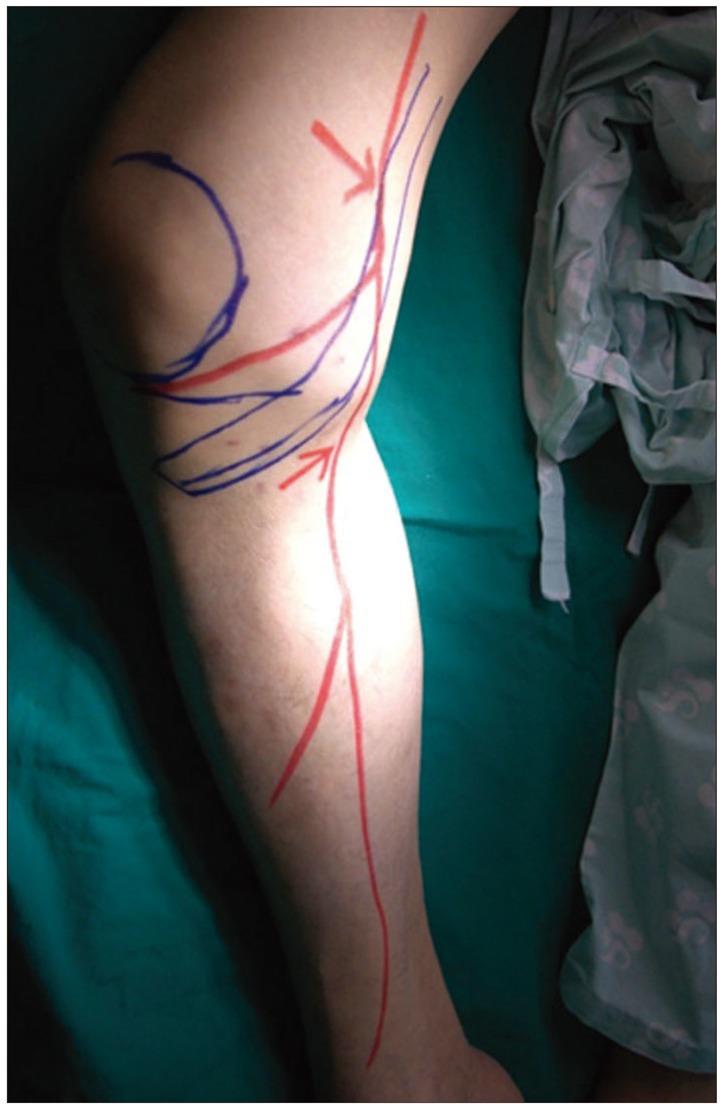

A 65-year-old male presented with pain in his right medial calf. An imaging study revealed no acute lesions, and a diagnosis of saphenous neuralgia was made by a nerve conduction study. He received temporary pain relief with saphenous nerve blocks twice in a one-week interval. Pulsed radiofrequency neuromodulation reduced pain to 10% of the maximal pain intensity. At 6 months after the procedure, the pain intensity was not aggravated even without medication. Pulsed radiofrequency neuromodulation of the saphenous nerve may offer an effective and minimally invasive treatment for patients with saphenous neuralgia who are refractory to conservative management.

一名65岁男性因右小腿内侧疼痛就诊。影像学检查未发现急性病变,经神经传导研究诊断为隐神经痛。他在一周内接受了两次隐神经阻滞,疼痛得到了暂时缓解。脉冲射频神经调节将疼痛减轻至最大疼痛强度的10%。术后6个月,即使未用药,疼痛强度也未加重。对于保守治疗无效的隐神经痛患者,隐神经脉冲射频神经调节可能提供一种有效且微创的治疗方法。